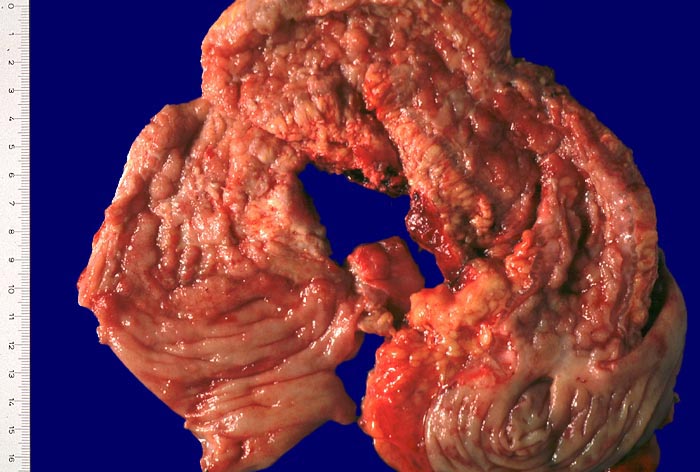

Die Verteilung der Läsionen im Darm ist sowohl makrokopisch (> 2884) als auch mikroskopisch (> 656) (> 409) diskontinuierlich und herdförmig ausgeprägt. Im Gegensatz zur Colitis ulcerosa können beim Morbus Crohn nicht nur das Kolon, sondern sämtliche Abschnitte des Gastrointestinaltraktes befallen sein. Am häufigsten ist das terminale Ileum zusammen mit dem Kolon befallen.

Makroskopisch typisch sind oberflächliche aphthöse Ulzera, gartenschlauchartige Strikturen im Dünn- und Dickdarm mit segmental verdickter und fibrosierter Darmwand, intramurale Abszesse, entzündliche Konglomerattumoren und verbackene Darmschlingen mit Fistelbildungen. Häufiger im Dünndarm als im Dickdarm findet sich das klassiche Pflastersteinrelief der Schleimhaut aufgrund rissförmiger Ulzera zwischen ödematösen Schleimhautarealen (> 369) Granulationsgewebspolypen oder Pseudopolypen (erhaltene Schleimhautinseln in Ulkusarealen) (> 408) finden sich beim Crohn seltener als bei der Colitis ulcerosa.

In Biopsien der Darmschleimhaut zeigen sich als Zeichen der Chronizität eine Architekturstörung, reepithelialisierte Schleimhautdefekte und metaplastische Veränderungen. Typisch für den Morbus Crohn sind entzündlich veränderte Schleimhautabschnitte neben weitgehend normaler Schleimhaut. In der Lamina propria findet sich ein verdichtetes gemischtes Infiltrat bestehend aus Lymphozyten, Plasmazellen, Makrophagen, neutrophilen und eosinophilen Granulozyten. Typisch für chronisch entzündliche Darmerkrankungen ist eine basal betonte Lymphoplasmozytose der Lamina propria. Die neutrophilen Granulozyten finden sich herdförmig in der Lamina propria, im Kryptenepithel (Kryptitis) und als Ansammlung in dilatierten Krypten (Kryptenabszess). Erhaltene Schleimhautabschnitte zwischen ulzerierten Arealen und Granulationsgewebe imponieren als entzündliche Pseudopolypen.